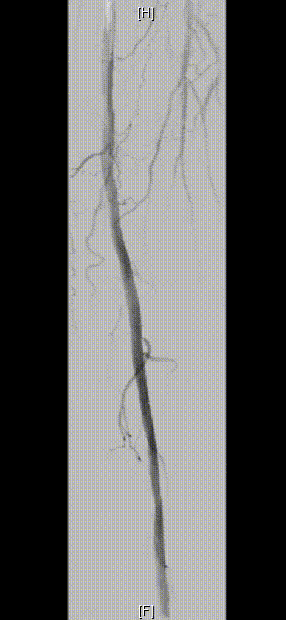

图为:股腘动脉DAART+区域性DES 最终造影

图为:2023年11月 2年后复查

2年后(2023-11)复查

下肢动脉CTA提示左股腘动脉通畅,DES区域未见内膜增生管腔丢失表现